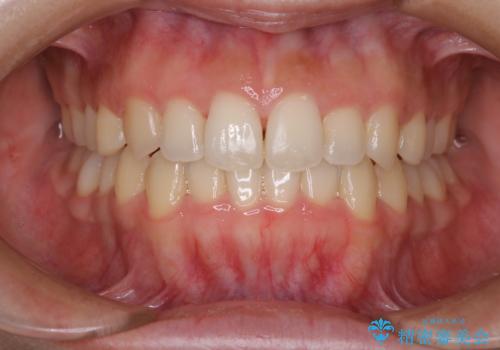

上下前歯が接触しない オープンバイトをインビザラインで改善

オープンバイト(開咬)を非抜歯インビザラインで治す